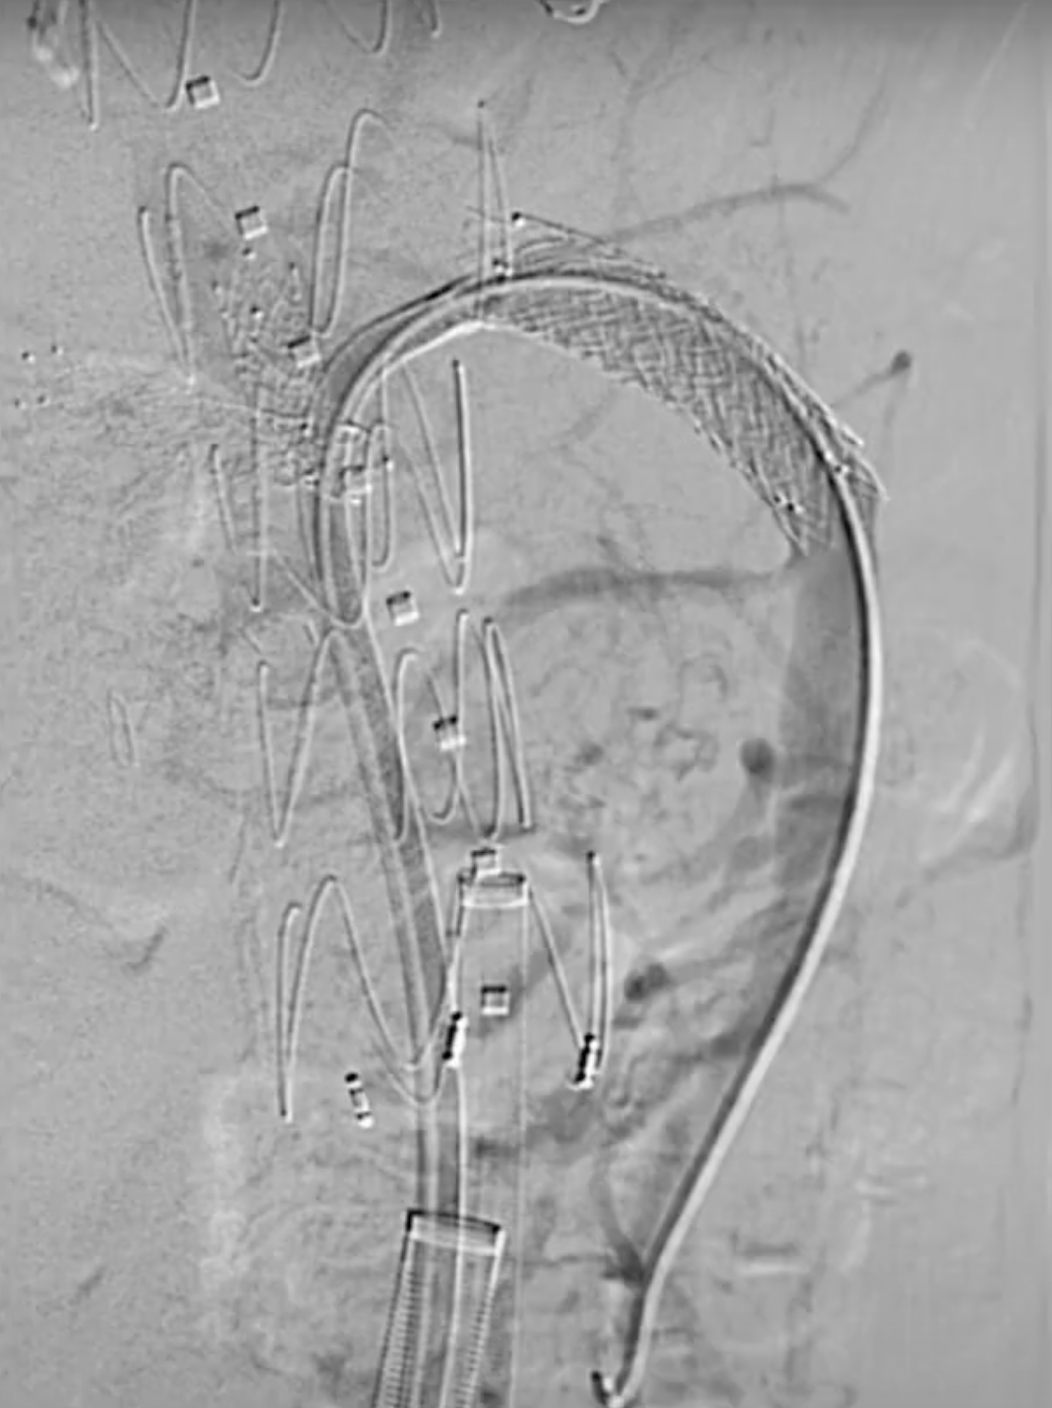

确认导丝进入靶血管后移除激光导管,依次使用4mm快交球囊、5mm切割球囊进行扩张开窗,交换入35系统导丝,在预植入的支架内引入VBX球扩覆膜支架,远端超过预植入支架远端,近端伸入主动脉3-5毫米,扩张球囊使VBX释放。

再次扩张VBX支架近端使其锚定于主动脉支架上。

最后进行内脏动脉部分主动脉造影。注意在肾下有足够的空间(约5cm)以植入后续支架。使用普通EVAR支架完成后续的工作。